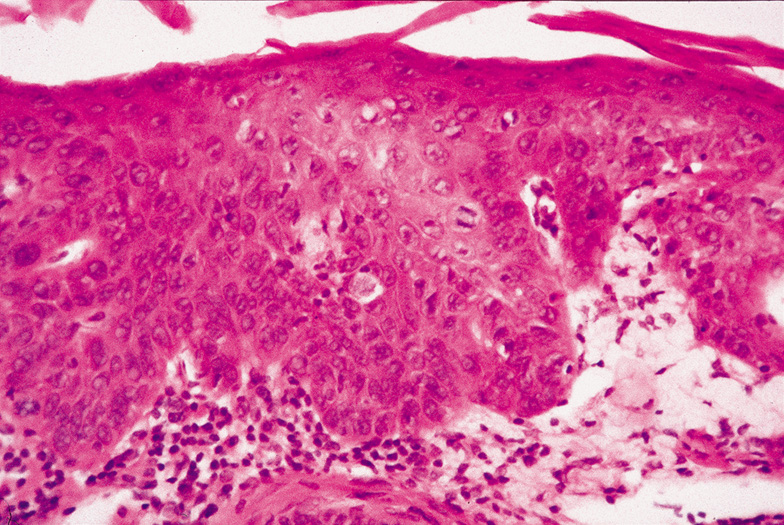

Dermoid Cysts Dermoid cysts are usually present at birth and commonly occur around the eyes. They may be adherent to the periosteum. Dermoid cysts are believed to result from sequestration of skin and its appendages along embryonic lines of closure and, thus, are commonly found at the frontozygomatic suture. Histologically, dermoid cysts are lined by epidermis possessing various mature appendageal structures (Fig. 22). These include hair follicles with terminal hairs, sebaceous glands, eccrine glands, and, occasionally, apocrine glands. Steatocystoma Steatocystoma may occur as solitary cysts (simplex) or multiple cysts (multiplex). The latter is often inherited as an autosomal dominant trait. These cysts are small and firm and, when punctured, exude an oily or creamy fluid. Steatocystoma is derived from cystic dilatation of the sebaceous duct, which empties into the hair follicle. Histologically, the cyst wall is folded and shows several layers of epithelial cells with a palisading of the peripheral cell layer. The cells lining the cystic cavity are covered by a thick, eosinophilic cuticle. Characteristically, flattened sebaceous lobules are present either within or close to the cyst wall. Pilomatrixoma Pilomatrixoma, also referred to as Malherbe's calcifying epithelioma, is a cyst derived from the hair matrix that forms the hair. It is often a solitary lesion and most commonly occurs on the face. Most pilomatrixomas occur in the first two decades of life and, if superficially located, produce a blue-red skin discoloration. Excision is curative. Histologically, pilomatrixomas show two types of cells in variable proportions: a basophilic cell with a dark basophilic nucleus and scanty cytoplasm and a “shadow cell,“ which has an unstained central nucleus and faintly eosinophilic cytoplasm (Fig. 23). There may be an abrupt or gradual transition between the two cells, and few or no basophilic cells may be seen in “old“ lesions. Calcification of pilomatrixoma is frequent and may occur within the shadow cells or in the stroma. The stroma usually is fibrotic and contains a foreign body reaction. Ossification also can occur occasionally. “Hybrid“ Cysts Follicular cysts with differentiation toward two or more of the previously mentioned cysts are referred to as hybrid cysts. Although originally described as a cyst of infundibular and trichilemmal keratinization, hybrid cysts may show any permutation of follicular keratinization. BENIGN TUMORS Epithelial Derivation FIBROEPITHELIAL PAPILLOMA (ACROCHORDON) The fibroepithelial papilloma, also known as a squamous papilloma, acrochordon or skin tag, is a polyp of skin that occurs commonly on or around the eyelids. Histologically, fingerlike projections of papillary dermis are covered by epidermis, which is of normal thickness and shows elongation of the rete ridges and hyperkeratosis. Dilated capillaries are seen in the dermis with a variable chronic inflammatory infiltrate (Fig. 24). If traumatized, there may be necrosis of the epidermis and dermis with ulceration and crust. SEBORRHEIC KERATOSIS. Seborrheic keratoses are the most common benign skin lesions in the geriatric population. They typically increase in size and number with age. Clinically, the lesions are well-demarcated, tan-to-brown papules or plaques with a rough, almost warty, “stuck on“ appearance. Due to their pigmentation, distinguishing the lesions from malignant melanoma is sometimes difficult. In some cases, seborrheic keratoses may be polypoid, resembling papillomas, or shiny and glistening, resembling basal cell carcinomas. Although clinically confused with both melanoma and basal cell carcinoma, they are not thought to be a precursor to malignancy. Histologically, seborrheic keratoses are composed of a proliferation of basaloid cells resembling the basal cell layer of the epidermis (Fig. 25). Six subtypes are recognized: acanthotic, hyperkeratotic, reticulated, clonal, irritated, and melanoacanthoma. All types show acanthosis, hyperkeratosis, and papillomatosis. Because the acanthosis produces an upward extension, the lower border of seborrheic keratoses is even, and a straight line can be drawn from one end of the tumor to the other. A characteristic feature of seborrheic keratoses are the horn pseudocysts, which are horny invaginations cut on cross section. Dermatosis papulosa nigra is a small, pigmented, polypoid seborrheic keratosis seen around the eyes and on the cheeks of Black people. The sudden appearance of numerous seborrheic keratoses, called the Leser-Trélat sign, may herald an internal malignancy. EPIDERMAL NEVUS. Epidermal nevi (nevus verrucosus) are linear verrucous plaques usually present at birth. The lesions may be localized or, rarely, generalized. The latter type may be associated with skeletal or central nervous system abnormalities (epidermal nevus syndrome). There are two major classifications of epidermal nevi: nonorganoid (keratinocytic) and organoid (sebaceous, follicular, and sweat gland). The type of epidermal nevus is determined by its predominant components, keratinocytes, or epidermal appendages. Histologically, there is considerable hyperkeratosis, papillomatosis, and acanthosis with fusion of the rete ridges. Epidermolytic hyperkeratosis may be seen in the localized or, more frequently, the generalized type. INVERTED FOLLICULAR KERATOSIS. Inverted follicular keratosis is a benign epithelial lesion occurring exclusively on hair-bearing surfaces and, most frequently, the face. Middle-aged or older individuals are usually affected. Clinically, the lesion presents as an asymptomatic, pink or flesh-colored papule or plaque. Rapidly growing lesions may be confused with keratoacanthomas. Histologically, inverted follicular keratoses are exoendophytic and symmetric. There is a bulbous proliferation of keratinocytes showing abundant eosinophilic cytoplasms into the dermis. Often, the stratum corneum is parakeratotic and contains neutrophils, serum, and red blood cells. A characteristic feature, which is also shared with irritated seborrheic keratoses, is the presence of squamous eddies, which are whorls of eosinophilic keratinocytes arranged in an onion-peel fashion (Fig. 26). Some authors believe that inverted follicular keratoses are really irritated seborrheic keratoses or verrucae with squamous eddies. WARTY DYSKERATOMA Warty dyskeratoma presents as an umbilicated keratotic papule resembling a keratoacanthoma, but can also be confused with a squamous cell carcinoma. It occurs primarily on the scalp, face, or neck. The characteristic histologic features are a cupshaped invagination filled with keratinous material and acantholytic, dyskeratotic cells. Villi of dermal papillae project into the base of the crater and are lined by a single layer of basal cells. Corps ronds, which are dyskeratotic cells containing a pyknotic nucleus surrounded by a clear halo, are seen in the granular layer at the entrance of the invagination (Fig. 27). The presence of acantholytic dyskeratosis with corps ronds is reminiscent of Darier's disease, but warty dyskeratoma is believed to represent a distinct cutaneous tumor with histologic resemblance to Darier's disease. Melanocytic Derivation MELANOCYTIC NEVUS. Nevi can be classified as ordinary nevi, spindle-cell nevi (Spitz), blue nevi, cellular blue nevi, plexiform spindle-cell nevi, or a combination of any of the above based on cell type and location (Fig. 28). Melanocytic nevi first appear as small, tan, flat macules around 6–12 months of age; they enlarge radially with body growth, and regress in later life. Clinically, they are distinguished from melanoma by their characteristic homogenous pigmentation, symmetric and well-defined borders, and smaller diameter (<5 mm). Pertaining to the periocular region, kissing nevi are congenital nevi that appear symmetrically on adjacent aspects of the upper and lower eyelids and are formed secondary to melanocytic migration to this aspect of the lids prior to separation of the embryonic eyelids. Histologically, nevi are composed of benign melanocytes with little pleomorphism or cellular atypia. The overall distribution of melanocytes is symmetrical and they tend to form nests. Melanocytes become smaller with less cytoplasm as they descend deeper into the dermis. Acquired melanocytic nevi can be classified histologically as junctional nevi (cells at dermoepidermal junction), intradermal nevi (cells found only in dermis, not at junction), and compound nevi (combined features of junctional and intradermal nevi) (Fig. 29). Increased risk of malignant transformation occurs as nests of nevus cells migrate from the epidermal to dermal region; thus, junctional and compound nevi more commonly have malignant transformation.